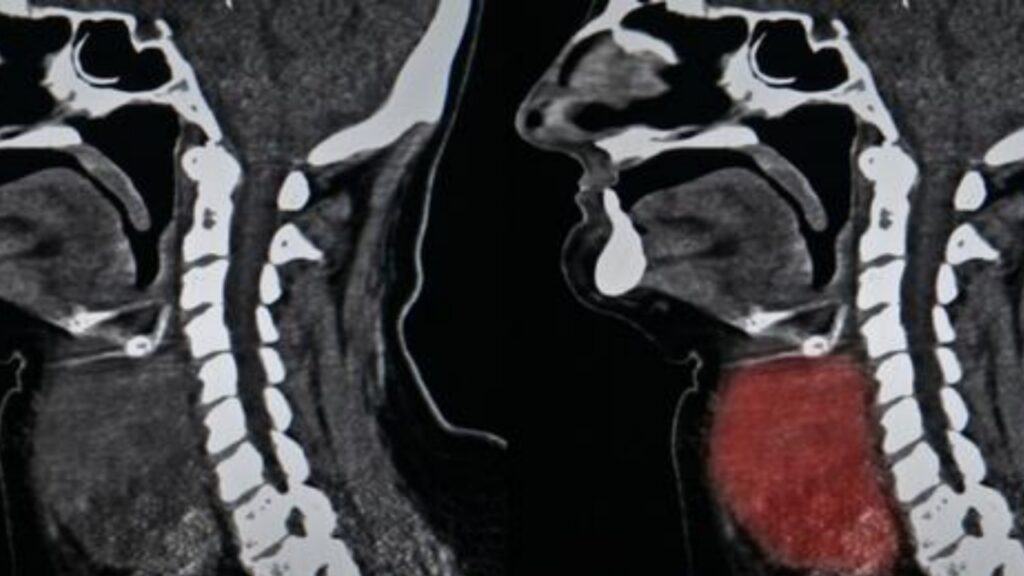

Come individuare per tempo il cancro alla testa o alla gola

Sulla base dei tessuti e degli organi coinvolti, il cancro alla testa e alla gola può essere di varia entità. Il più comune è quello della tiroide, ma può altresì riguardare le ghiandole salivari.